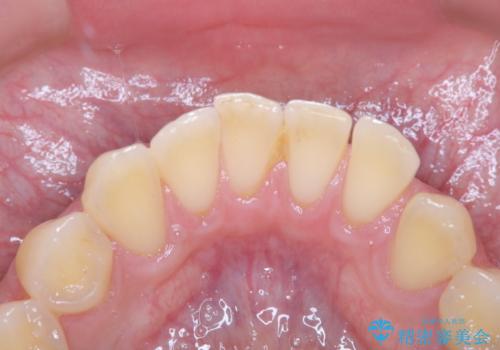

- 数年ぶりに歯科へ来院とのこと。全体的に歯のクリーニングをしてほしいとのことでした。

PMTC60分コースを行いました。